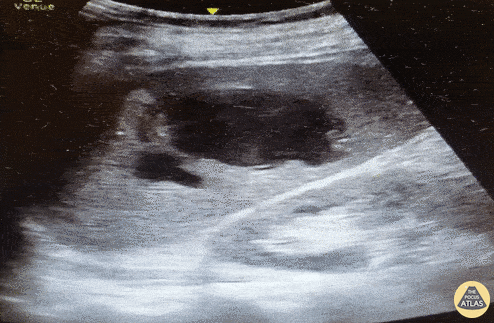

Trauma - Splenic hematoma with active extravasation

72 year-old male on Eliquis presented to the ED hypotensive after a fall. He was found to have left-sided rib fractures and ecchymosis. FAST was negative for intra-abdominal free fluid, pulmonary effusion, and pneumothorax but did show a splenic hematoma with a fluid jet and swirl (seen here). IR read the CTA as no active extravasation. After describing the ultrasound images the pt was taken to IR and had splenic artery angiography which confirmed extravasation, and was subsequently embolized with resultant hemodynamic stabilization. Dr Alec Glucksman PGY-III @alecglucksman, Dr Anna Van Tuyl, Dr Norman Ng, Dr Joshua Greenstein Northwell Health - Staten Island University Hospital